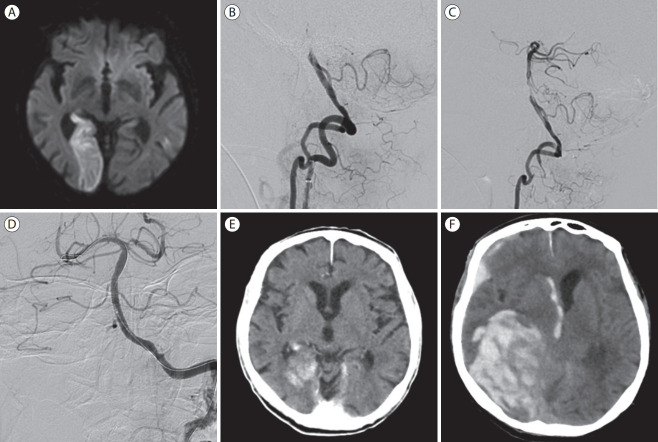

Abstract Image